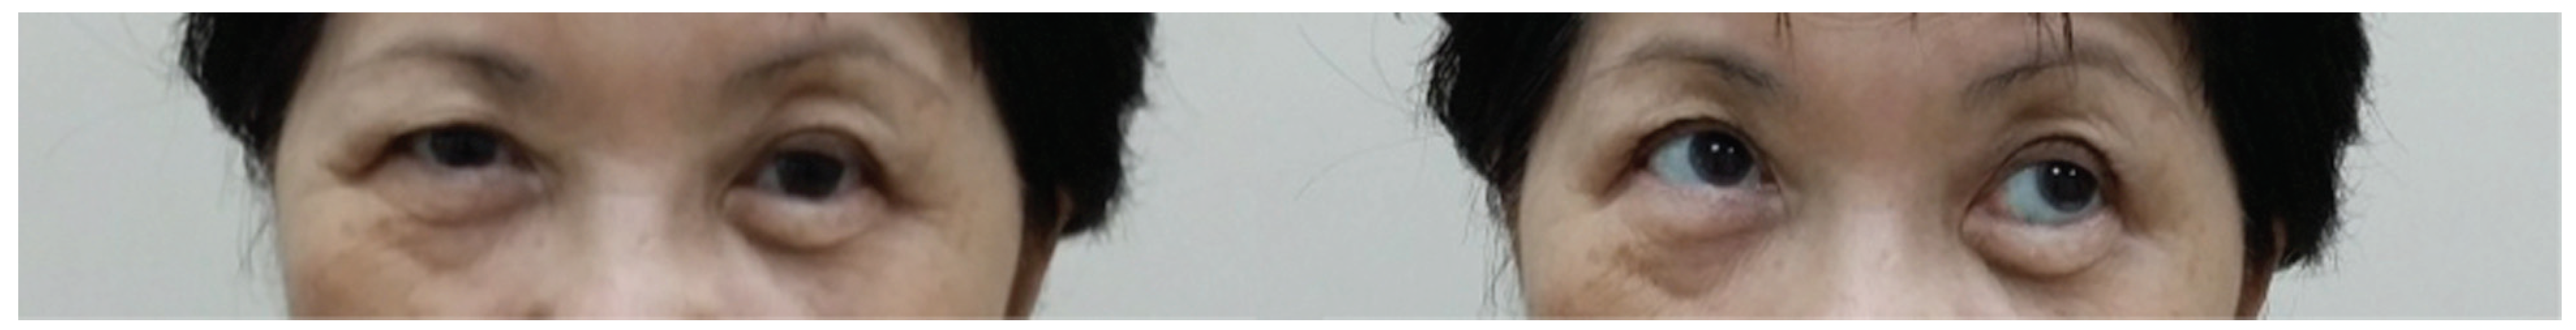

A 40-year-old man underwent an open reduction internal fixation (ORIF) of his right zygomaticomaxillary complex (ZMC) fracture and orbital floor reconstruction for a right orbital floor fracture, sustained after a road traffic accident (Figure 1). He had no preoperative diplopia.

The surgery took place 10 days following the accident due to neurosurgical concerns regarding his brain injury. Intraoperatively, the periorbita surrounding the herniated contents was noted to be disrupted. A 0.4-mm titanium curved plate was used to reconstruct the orbital rim, and the medium 0.4-mm precontoured titanium orbital plate (Figure 2) was used for reconstruction of the orbital floor defect (DePuy Synthes, Johnson & Johnson, Solothurn, Switzerland). Intraoperatively, he had a negative forced-duction test and postoperatively, he was noted to have full range of extraocular movements of his right eye. The postoperative CT scan demonstrated anatomical placement of the orbital floor plate with reduction of all periorbita (Figure 3).

Figure 1. Coronal and sagittal cuts of the CT scan of the face (Case 1) demonstrating the presence of a large right orbital floor defect (arrows).